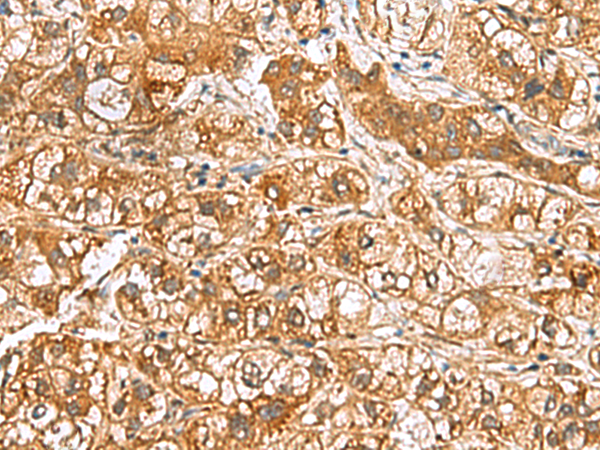

分类: 科研抗体货号: P10237别名: TIH1应用: IHC反应种属: Human, Mouse, Rat